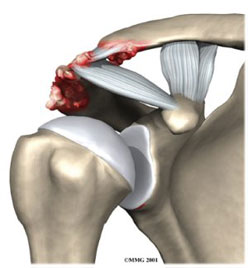

Βλάβη SLAP

Αυτή η βλάβη είναι στο άνω τμήμα της γλήνης στο σημείο που εκφύεται

η μακρά κεφαλή του δικεφάλου μυός και ο επιχείλιος χόνδρος μαζί

Η θεραπεία είναι ο καθαρισμός της βλάβης και η επανακαθήλωση

της μακράς κεφαλής του δικεφάλου μυός και του επιχείλιου χόνδρου

με τη βοήθεια αρθρωσκοπικών αγκυρών.